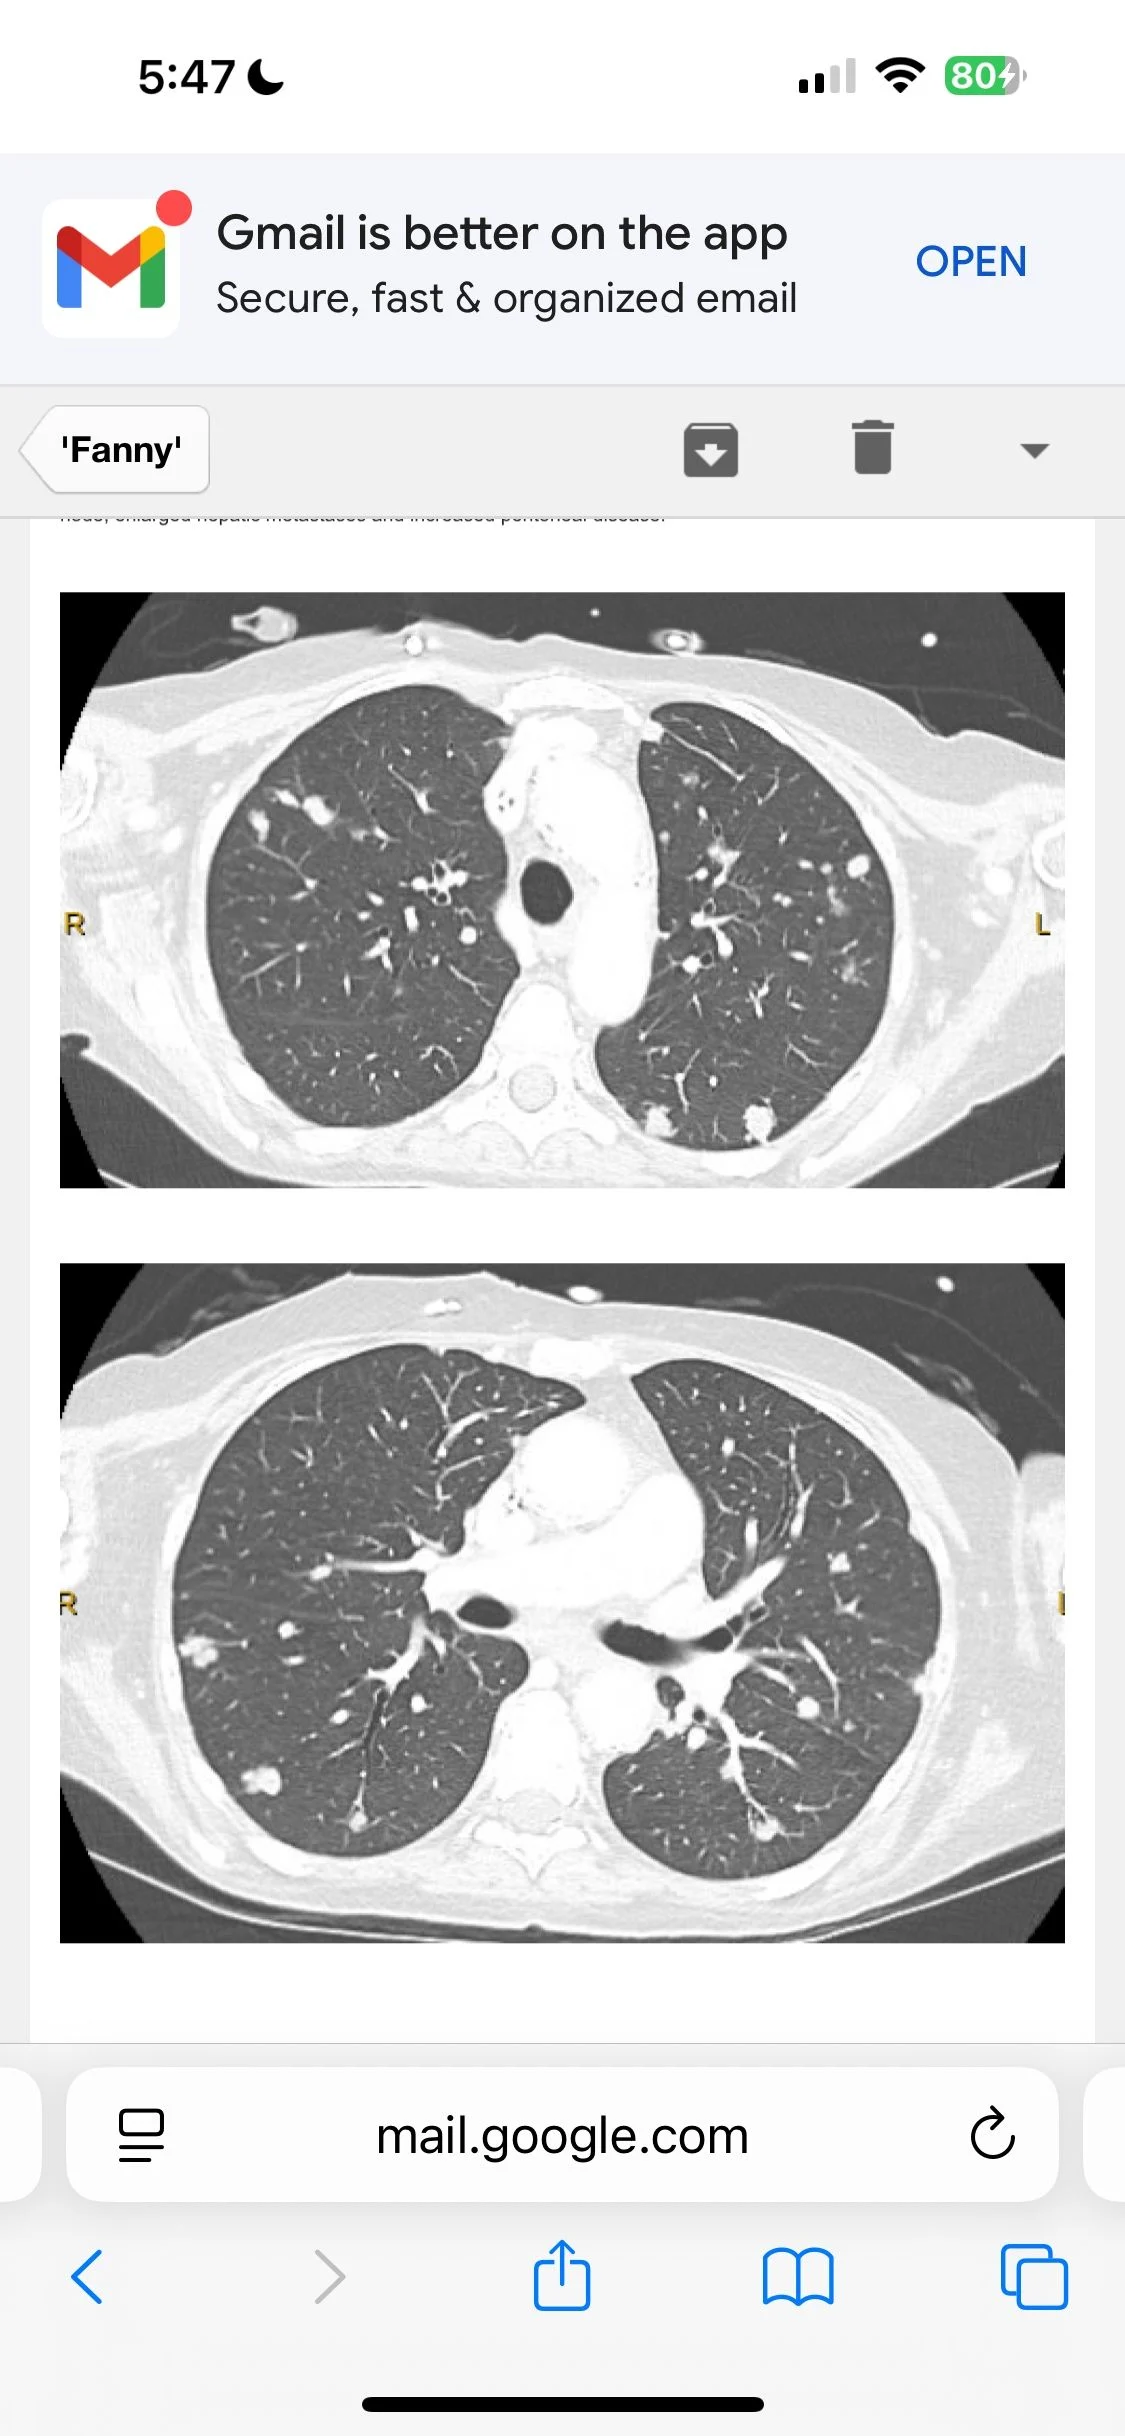

Dr. Limaye presented a challenging case of EGFR (Exon 19 deletion) and MET-Amplified non TTF1 expressing metastatic lung adenocarcinoma that presented with ovary involvement. The tumor had p53 mutation, CDKN2A/B deletion.

Discussion focused on targeting EGFR and MET in her ongoing therapy.”